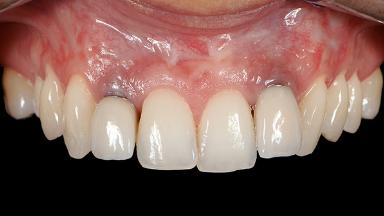

Paolo Casentini demonstrates that peri-implantitis can be successfully treated even at an advanced stage. He discusses a case in which the existing implants and prostheses were both retained while regenerating the defect and creating a band of keratinized tissue. A 69-year-old female patient was referred by her general dentist for evaluation of a recurrent infection at previously placed and restored implants in the posterior left mandible. The patient’s chief complaint was recurrent swelling and pain in the molar region of the left posterior mandible with discomfort during brushing in the same area. The patient reported receiving two implants (36 and 37) nine years earlier.